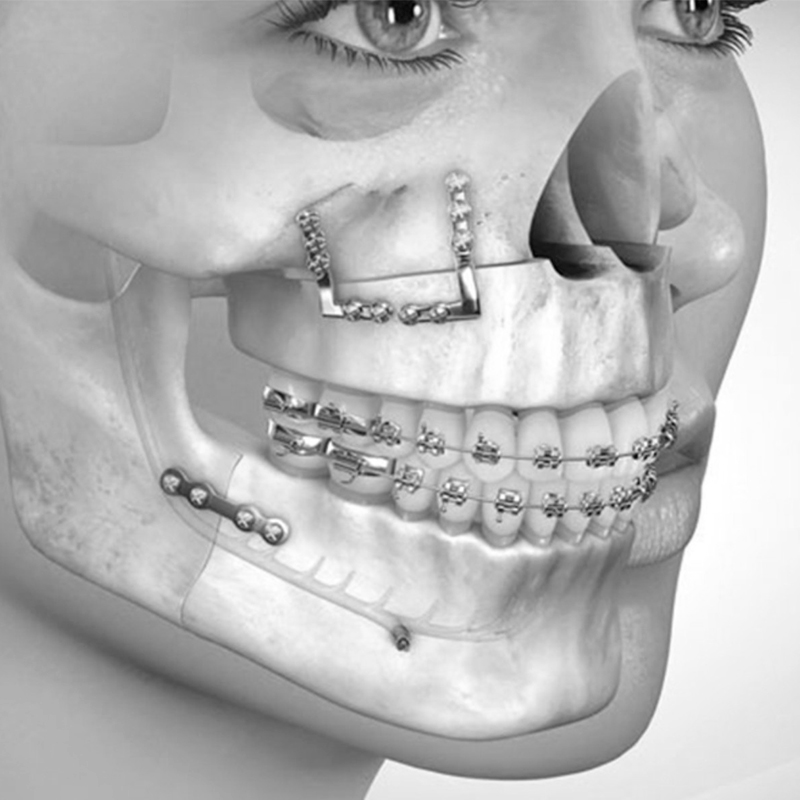

A Cirurgia Bucomaxilofacial é uma especialidade da odontologia responsável pelo tratamento de doenças relacionadas com a cavidade oral, seus anexos, fraturas ósseas faciais e disfunções das articulações temporomandibulares. O Cirurgião Buco Maxilo pode realizar as cirurgias tanto em ambientes hospitalares como em consultórios odontológicos.

Ortodontia é uma especialidade odontológica que corrige a posição dos dentes e dos ossos maxilares posicionados de forma inadequada. Dentes tortos ou dentes que não se encaixam corretamente são difíceis de serem mantidos limpos, podendo ser perdidos precocemente, devido à deterioração e à doença periodontal.